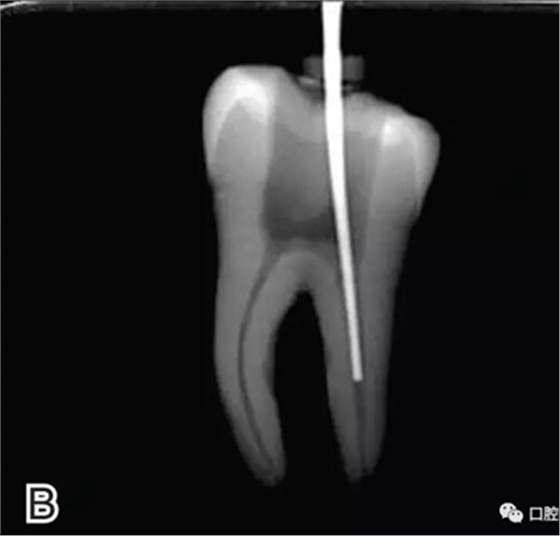

3、試尖

選擇非標(biāo)準(zhǔn)牙膠尖(如0.04、0.06 錐度牙膠尖)作為主尖,型號(hào)一般與根管預(yù)備最大號(hào)的器械型號(hào)一致,能到達(dá)距根尖0.5~1 mm 處,主尖尖段與根管壁緊密接觸。拍試尖X 線片進(jìn)行確認(rèn)(圖3)。

圖3 試尖,A.試主尖 B.拍試尖X片